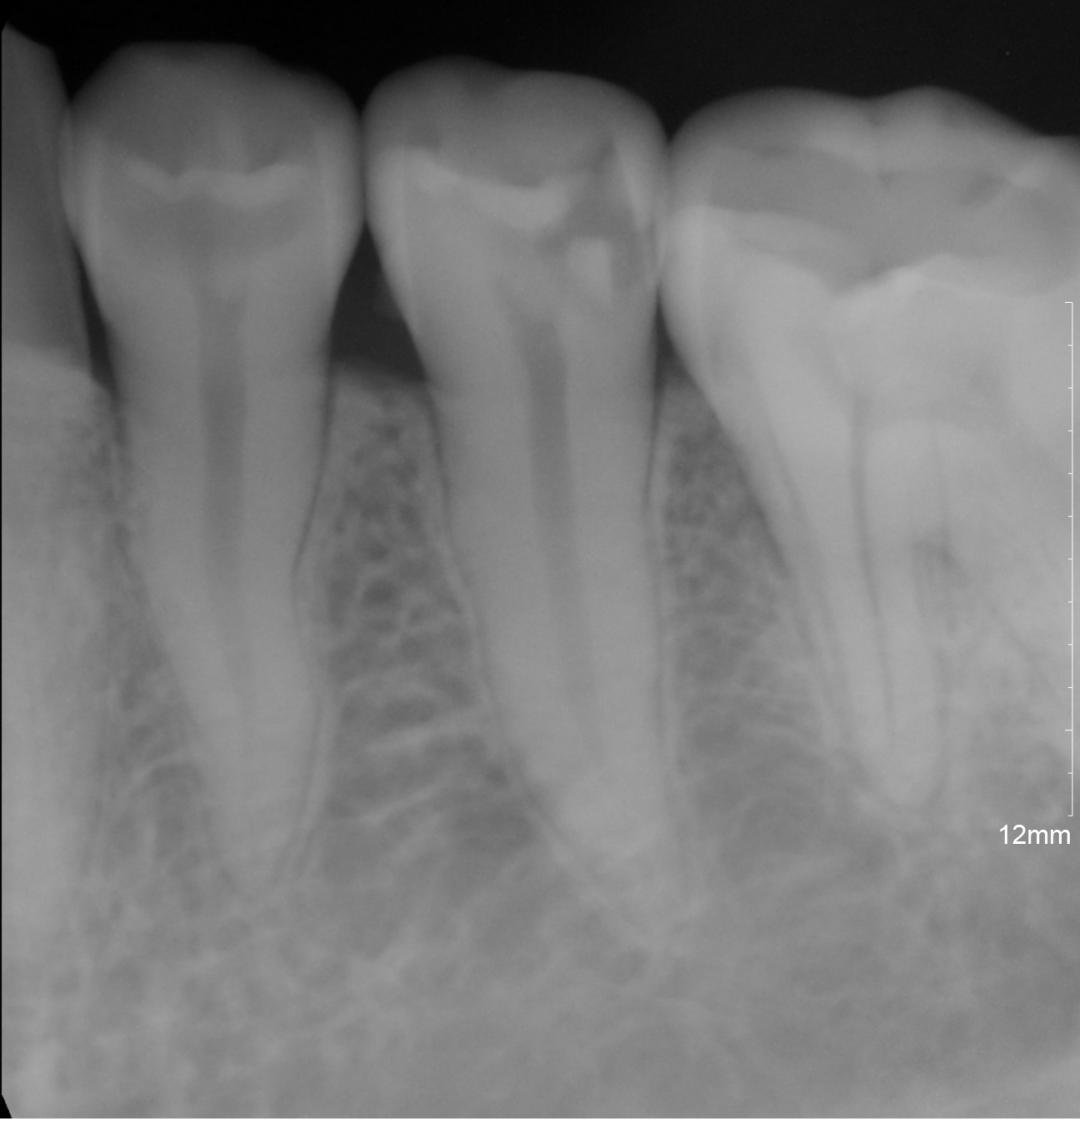

必要时可自窦道口插入诊断丝

拍摄X线示踪片以确定窦道的来源。

( 根管治疗前后对比图)